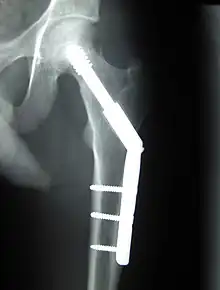

- Chirurgie orthopédique

- Prothèses articulaires (hanche, coude, genou, poignet…)

- Réparation de fractures (vis, plaques, clous, broches)